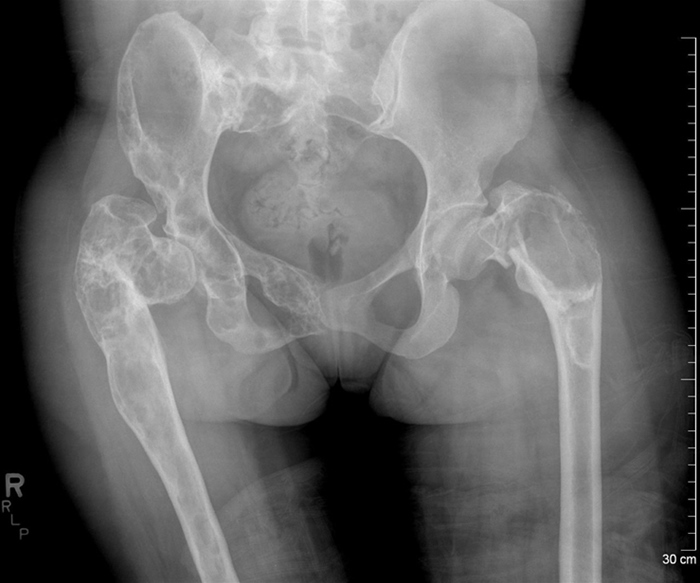

A 29-year-old woman is evaluated for severe left hip pain after twisting her leg.  She has bony deformities of the lower extremities, and her mobility is limited.  The patient has a history of hyperthyroidism, which was managed with radioiodine therapy.  Menarche was at age 7, and she has regular 30-day cycles.  Physical examination shows large, hyperpigmented macules with irregular borders located on the left shoulder, left side of the neck, and left buttock.  X-ray findings are shown in the image below. A 29-year-old woman is evaluated for severe left hip pain after twisting her leg.  She has bony deformities of the lower extremities, and her mobility is limited.  The patient has a history of hyperthyroidism, which was managed with radioiodine therapy.  Menarche was at age 7, and she has regular 30-day cycles.  Physical examination shows large, hyperpigmented macules with irregular borders located on the left shoulder, left side of the neck, and left buttock.  X-ray findings are shown in the image below.   Which of the following is the most likely diagnosis? A) Ewing sarcoma B) Gaucher disease C) Legg-Calvé-Perthes disease D) McCune-Albright syndrome E) Neurofibromatosis type 1 Which of the following is the most likely diagnosis?